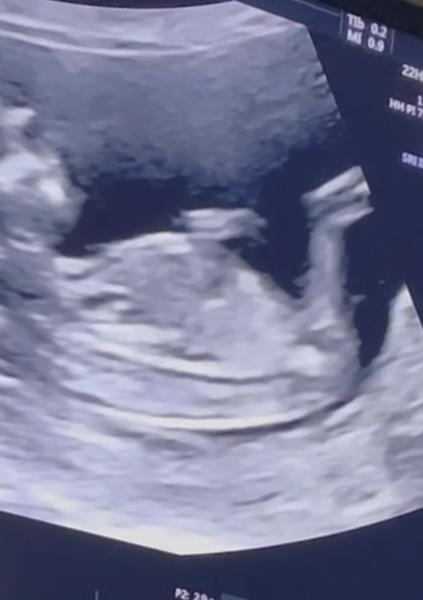

ráda bych se zeptala, zda jde určit pohlaví u našeho miminka 12+4tt.

bohužel, z těchto fotografií to odhadovat nelze. ☹